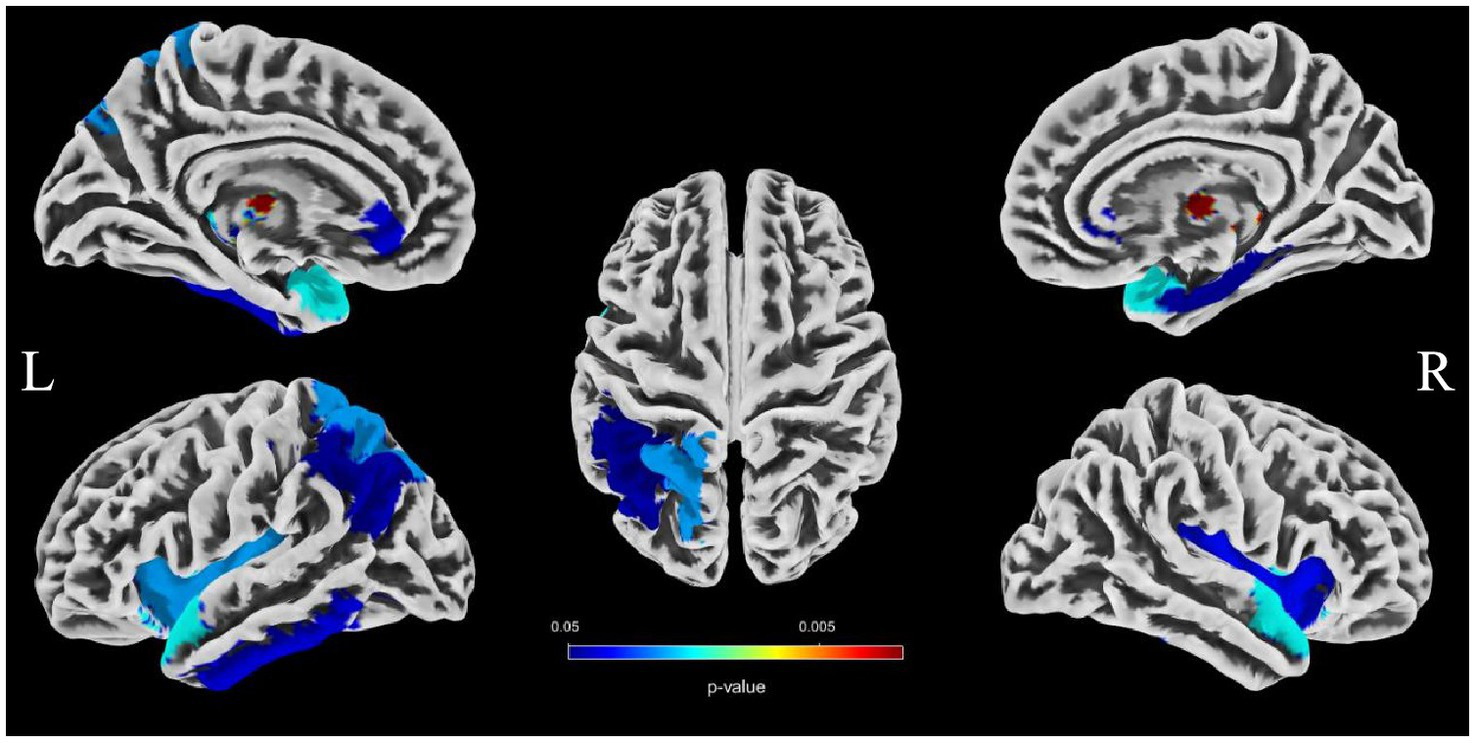

Association between the morphologic features of intracranial distal arteries and GMV in different brain regions

To evaluate the associations between intracranial distal vascular features and GMV in different brain regions, partial correlation analysis with a one-tailed method was performed, controlling for gender, age and TIV. The AAL3 atlas was used to label statistically significant areas in the result reporting. The correlation analysis results are shown in Tables 6, 7, and the corresponding GM regions images are shown in Figures 4, 5. However, we did not find distal artery density related GM regions at our statistical cut off of FDR <0.05. No brain regions correlated negatively with these cerebrovascular characteristics.

Figure 4

Images showing GM regions where distal artery length is positively associated with GMV (p < 0.05, FDR correction).

Figure 5

Images showing regions where average tortuosity of distal arteries is positively associated with GMV (p < 0.05, FDR correction).

Brain atrophy is a condition characterized by the loss of neurons and their connections, which can either be generalized or focal. Focal cerebral atrophy and the associated damage can affect specific areas of brain tissue, leading to corresponding functional impairments (34). Brain atrophy is also a crucial MRI marker in CSVD. Many studies reported an association between CSVD and brain atrophy, including global atrophy, corpus callosum atrophy, central atrophy (increased ventricular size and atrophy of the basal ganglia), mesencephalic atrophy, and hippocampal atrophy, as well as focal cortical thinning in brain regions connected to subcortical infarcts (3, 15, 16). Hippocampal and medial temporal lobe atrophy could contribute to cognitive impairment even in the absence of Alzheimer pathology (9, 35, 36). Alternatively, medial temporal lobe atrophy might associate with executive function impairment (37). A combined continuous measure of four imaging findings, including WMHs, lacunar, cerebral GM, and hippocampal volumes, had the greatest independent predictive value for both cognitive and functional outcome in older individuals with≤7 years follow-up (38). In additional that the CSVD-induced thalamic atrophy could mediate the effects of CSVD on slower walking speed in the elderly (8). Our study investigated the associations between distal arterial morphological features and brain atrophy indicators in CSVD. The results indicate that both distal artery length and density were positively correlated with GM fraction in CSVD patients, regardless of whether univariable or multivariable linear regression analyses were performed. In addition, distal artery length and density were also found to be negative associated with CSF fraction, although this relationship disappeared after adjusting for potential confounders. In further subgroup analysis, we also found that participants in the highest distal artery length tertile had significantly higher GM fraction and lower CSF fraction than participants in the lowest distal artery length levels. However, we did not find a significant association between average tortuosity and different brain structures. These results strongly suggested an intricate relationship between distal arterial features and different brain structures. To further investigate the relationship between distal arterial features and local changes in GMV, we divided GM into 170 regions using the AAL3. The study findings indicate a clear association between distal arterial morphologic features and regional GMV, as presented in Tables 6, 7. The corresponding GM regions images are depicted in Figures 4, 5. The parahippocampal gyrus (PHG), angular gyrus (ANG), anterior cingulate cortex (ACC), and insula (INS) are predominantly involved in emotion, cognition, and memory functions. Reduced GMV in these regions may lead to corresponding functional impairment. Furthermore, reductions in GMV in cerebellar structures are linked to symptoms of dizziness and unsteady gaits in patients with CSVD. A significant proportion of these GM nuclei are subcortical nuclear (caudate, putamen, pallidum, and thalamus), which play vital roles in motor control functions. Atrophy of these regions has been associated with worse walking performance in CSVD patients (8, 39, 40). The potential reason may be related with the following factors. The deep nuclei are vulnerable to direct ischemic or hemorrhagic damage associated with CSVD due to their surrounding small perforating arteries from the middle and posterior cerebral arteries (41, 42). Compared to larger arteries, the morphological characteristics of the distal arteries we studied may be more relevant to changes in these perforating arteries. Currently, there are limited studies on the association between cerebrovascular structure and CSVD. In a community-based cohort study, Zhang et al. (43) found that the detailed structural alterations in cerebral vessel radius, tortuosity, and density were correlated with WMHs. A cross-sectional study investigation conducted on young adults has revealed that there exists an inverse correlation between brain vessel density and WMHs lesion counts. This finding suggests that the vascular morphology of an individual might influence their white matter resilience and potential to withstand risk exposures (44). In another study, it was observed that an increase in carotid lumen diameter is associated with a higher prevalence of lacunar infarcts and WMHs volume (45). This could serve as a compensatory mechanism to counteract the increase in stiffness and thickness of the arterial wall, thereby maintaining arterial compliance in the normal values (46–48). All of aforementioned studies were restricted to the entire cerebral artery or the larger artery, while our investigation specifically targets the smaller artery. As widely recognized, CSVD encompasses a range of conditions characterized by pathological changes primarily affecting small blood vessels with a diameter ranging from 40-200 μm in the brain. Nonetheless, we were unable to quantitatively evaluate these vessels directly. Inadequate perfusion of small arteries may lead to decreased blood flow in the upstream arteries, resulting in morphological alterations in vascular features as observed on 3D-TOF MRA (25). These features are mainly derived from the distal arteries (A2, M2, P2 and more distal). In this study, as anticipated, we found that distal arterial morphologic features on 3D-TOF MRA are associated with total or regional brain volumes/atrophy of CSVD. This finding provides valuable information to clarify the relationship between vascular health indicators and brain atrophy, and offers new evidence for a possible vascular origin of brain atrophy.